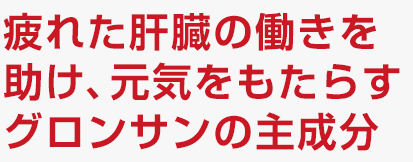

疲れの原因には「脳の疲労」「エネルギー源の不足」「疲労物質の蓄積」「神経と筋肉の接合部の異常」など、さまざまなものがあります。その中の「疲労物質の蓄積」と密接に関わっているのが肝臓です。

身体の代謝により体内にアンモニアなどの老廃物が発生。健常時は、肝臓内で尿素になり体外へ排泄されますが、疲労時はすべてを処理できません。処理しきれなかった老廃物は、脳の神経を刺激して、老廃物を抑える指令――つまり、体を休めさせる為に身体の動きを鈍くさせることが疲労感につながるのです。

具体的には、下記の疲労感となって現れます。

- ・眠気やだるさなど「活力の低下」

- ・いらいら、焦燥、集中力の低下などの「気力の低下」

- ・肩こりや口渇、頭痛など「身体違和感」

疲れをとるためには肝臓の働きを元気にし、「疲れ」の原因である「老廃物・有害物質」を体外へ排泄する機能を促進することが必要なのです。